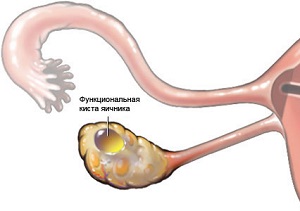

Кісти яєчників і вагітність